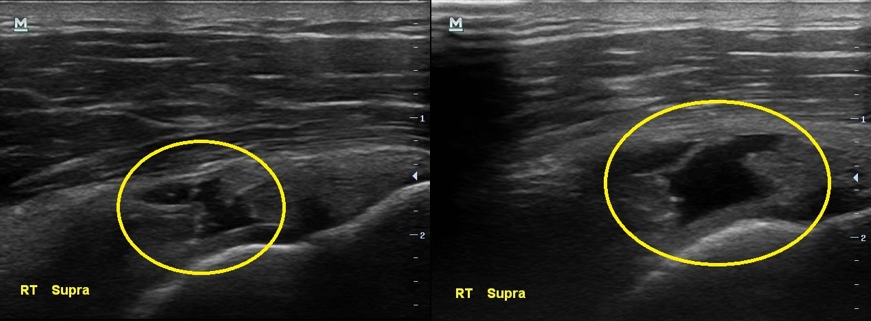

3개월만에 통증이 더 심해졌다고 찾아온 남자분, 검사 결과는 3개월전보다 더 악화 되었습니다.

초음파 검사 결과 3개월전에 비해 극상근 힘줄의 파열 정도가 더 심해져있습니다.

나 : 초음파 검사 결과가 더 나빠졌는데요...

나 : 초음파에서 이정도 소견이면..... MRI 촬영하고 필요하면 수술도 고려해보아야 할 정도네요